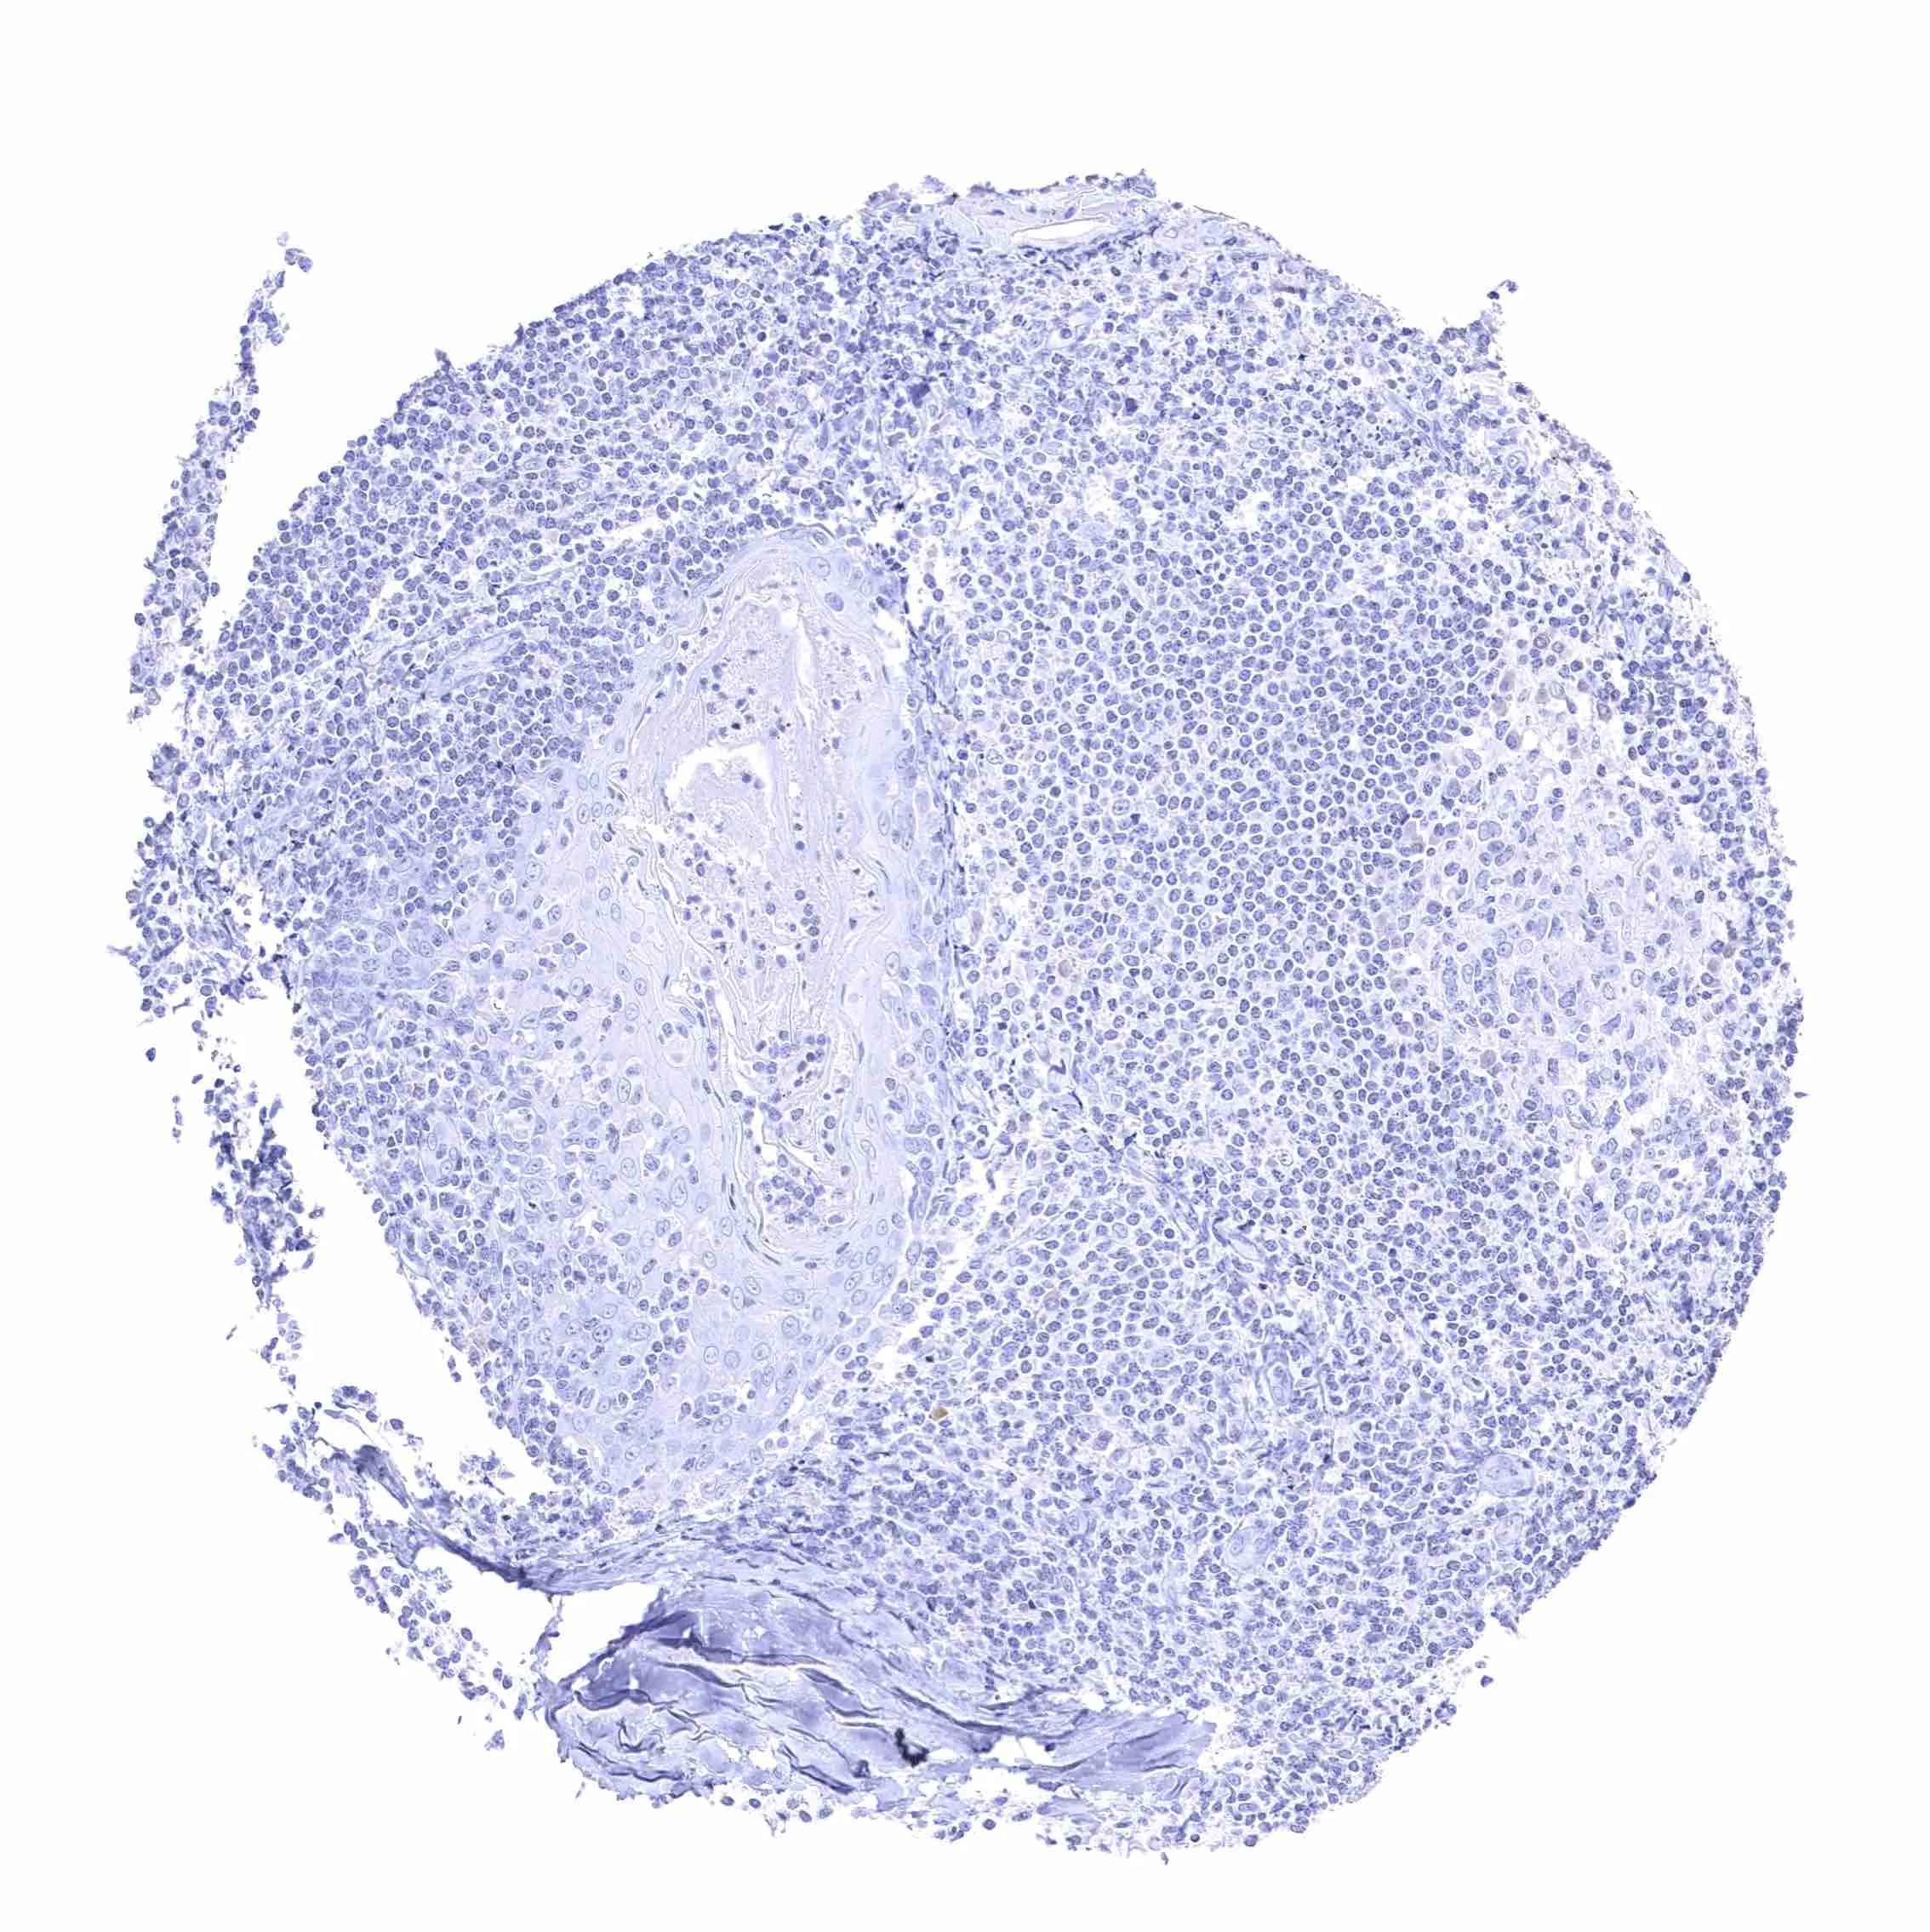

Tonsil